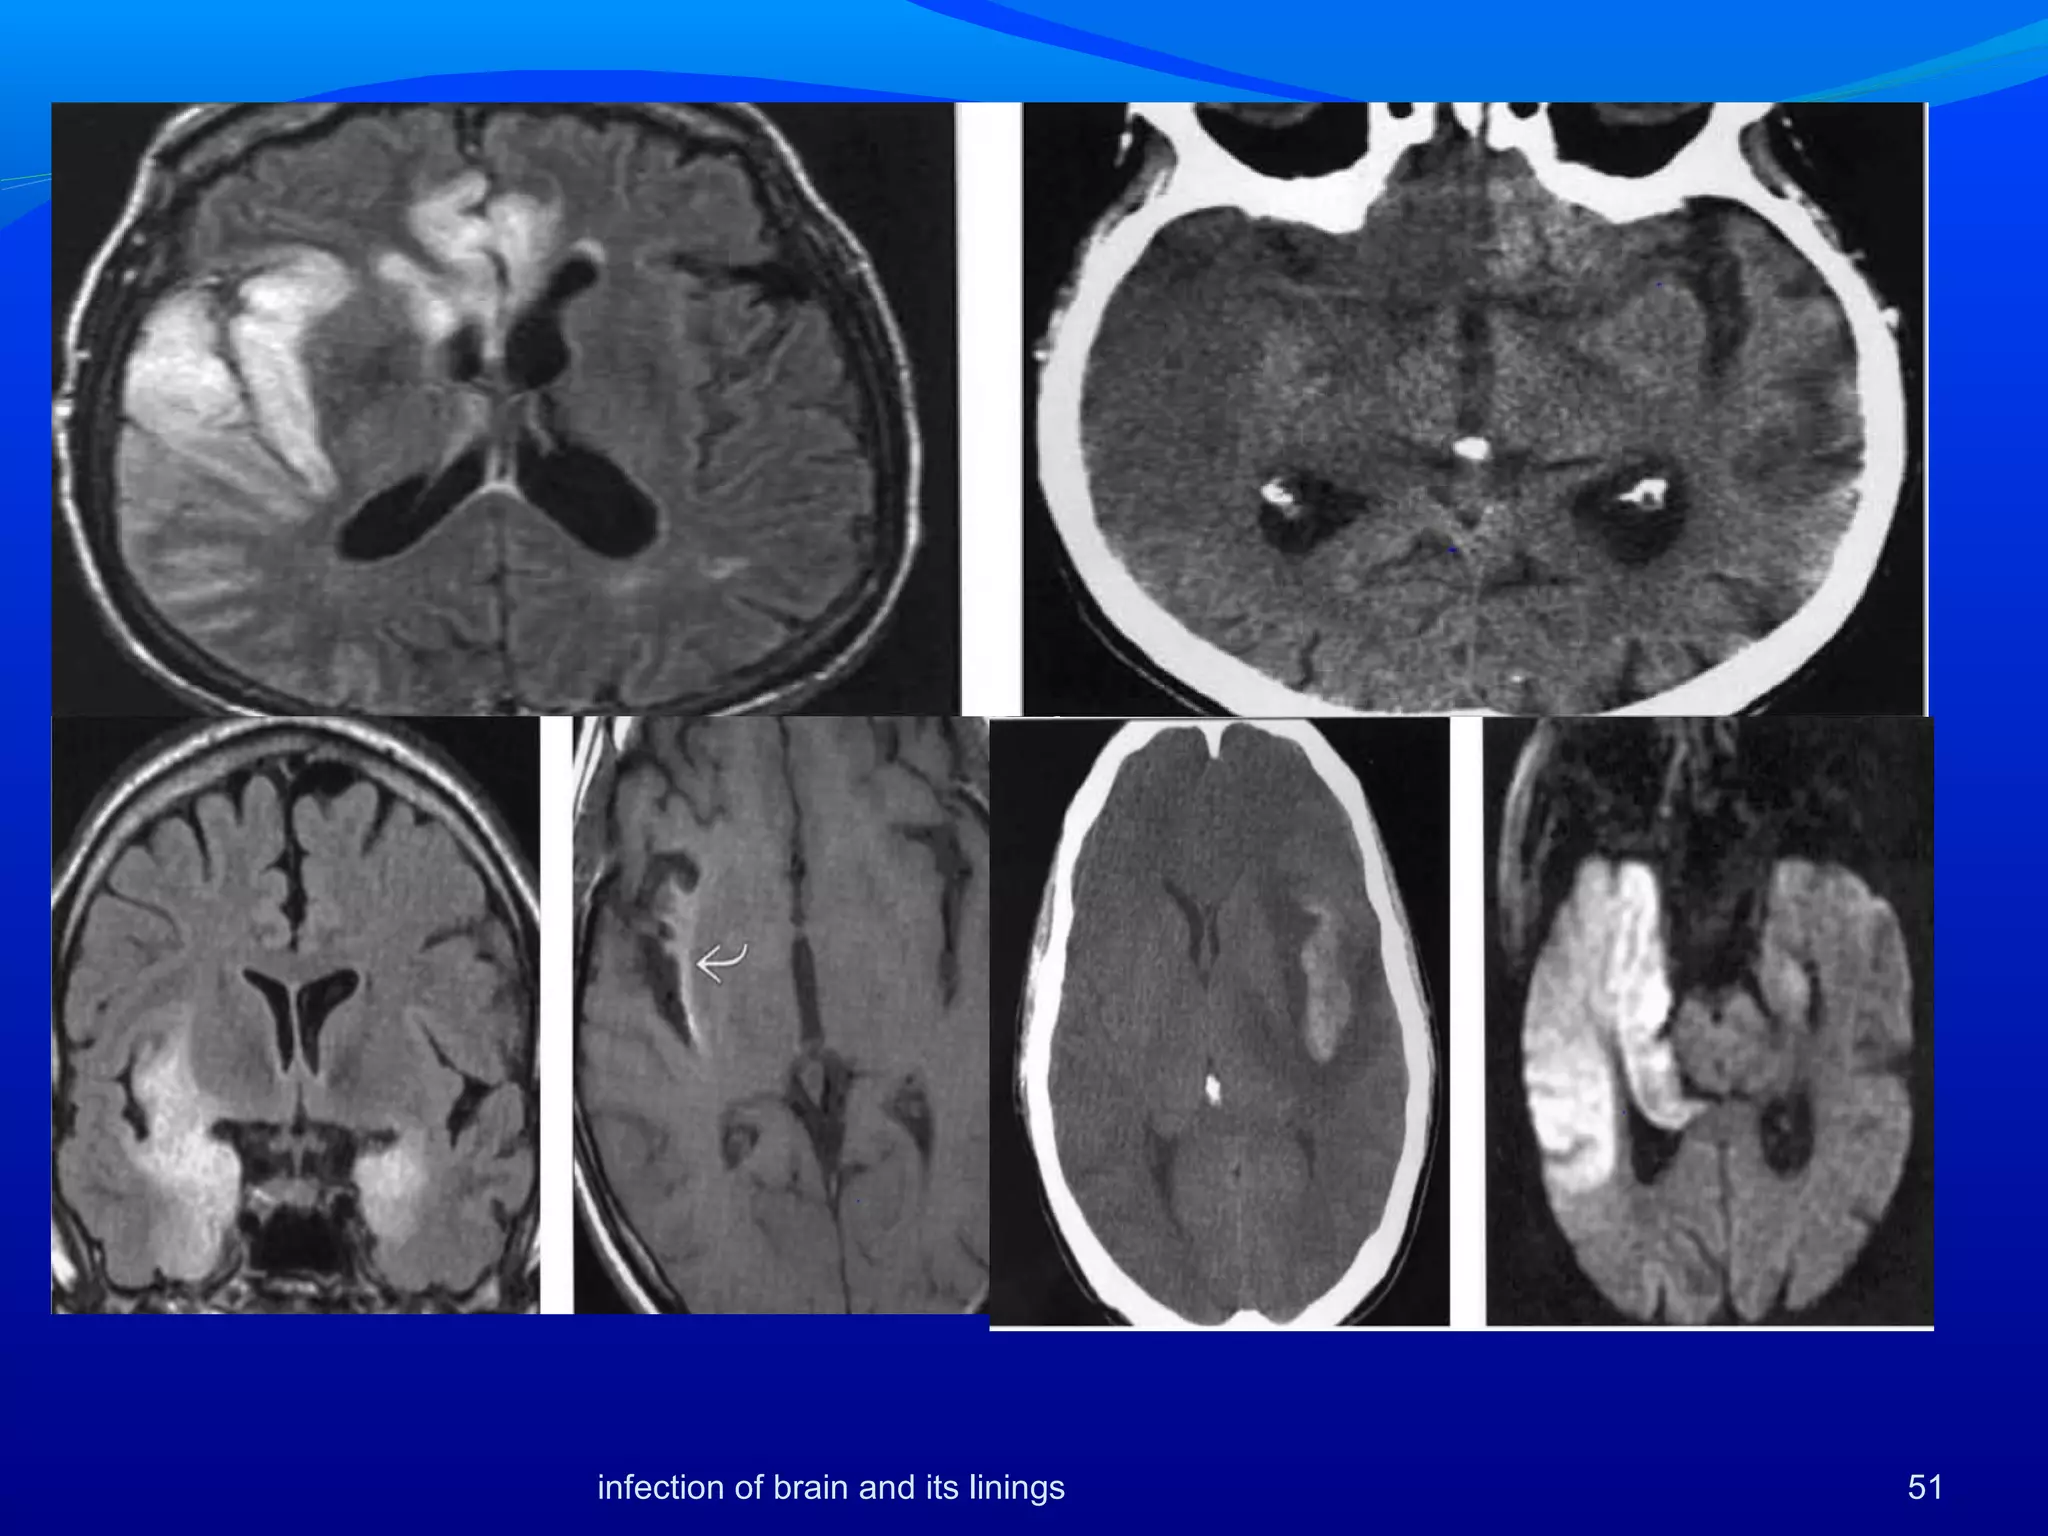

Usually bilateral

Hemorrhage and enhancement seen

Basal ganglia tend to be spared or involved in

contiguity with the TL.

Pons may be involved [Tien AJR:161,1993]

MR is more sensitive and shows lesions earlier than

CT or SPECT

Herpes simplex encephalitis

51infection of brain and its linings

Rare paraneoplastic syndrome

limbic system, often bilateral

Active seizures may disrupt BBB, cause

signal

abnormalities and enhancement